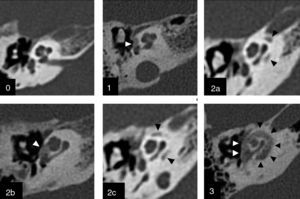

Para la descripción de la ubicación y extensión de las placas de otoespongiosis, en el año 2005 Symons y Fanning proponen un sistema de graduación basado en la distribución de la desmineralización ósea de la cápsula ótica13, que complementa la clasificación propuesta por Rotteveel et al el año 200414. Esta nueva clasificación hace énfasis en la diferencia pronóstica dada por la presencia de focos aislados de otoespongiosis versus compromiso difuso por la enfermedad, siendo aplicada para las formas fenestral y retrofenestral. Otro elemento importante es que esta clasificación ha demostrado tener buena concordancia intra- e interobservador, lo cual fortalece su aplicación en la práctica clínica3. Se resume la clasificación en la tabla 3, y se presentan ejemplos de los distintos grados en la figura 1.

Graduación por TC de la otoesclerosis. Clasificación de Symons y Fanning13 para graduar el compromiso de la otoesclerosis. Grado 0: Normal. Grado 1: Solo compromiso fenestral. Grado 2: Compromiso coclear parcheado (2a: giro basal; 2b: ápice/giro medio; 2c: giro basal y ápice/giro medio). Grado 3: Compromiso coclear difuso. Todas las imágenes corresponden a cortes axiales de oído derecho en el nivel de la cóclea. Las cabezas de flecha señalan las áreas de hueso espongiótico.

El sistema de graduación propuesto por Symons y Fanning, para la descripción de la ubicación y extensión de las placas de otoespongiosis13, es válido para la forma coclear, tal como para la forma fenestral (fig. 1).